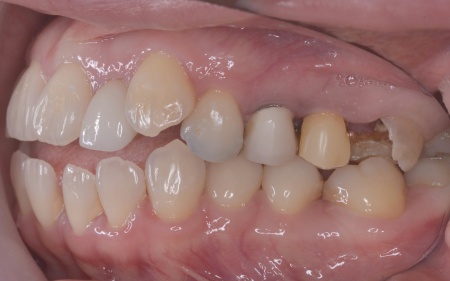

40代女性 矯正治療で噛み合わせを整えたあとセラミックの被せ物・詰め物で修復した症例

また、噛み合わせを確認したところ、奥歯で噛み合わせた際に上下の前歯が当たらず隙間ができる開咬(かいこう)が認められました。

開咬は前歯で食べ物を噛み切りにくくなるだけでなく、噛む力のバランスが崩れて奥歯に負担が集中しやすくなります。

修復治療が必要でしたがこの噛み合わせの問題を改善しないまま行うと、治療した歯に再び過度な力が加わって被せ物の破損・脱離や虫歯の再発を招くリスクが高まります。

まずは矯正治療を優先し、噛み合わせが整ってから虫歯の再発リスクの低いセラミックの被せ物・詰め物などで歯の形態と機能を回復する方針を提案し、同意いただきました。